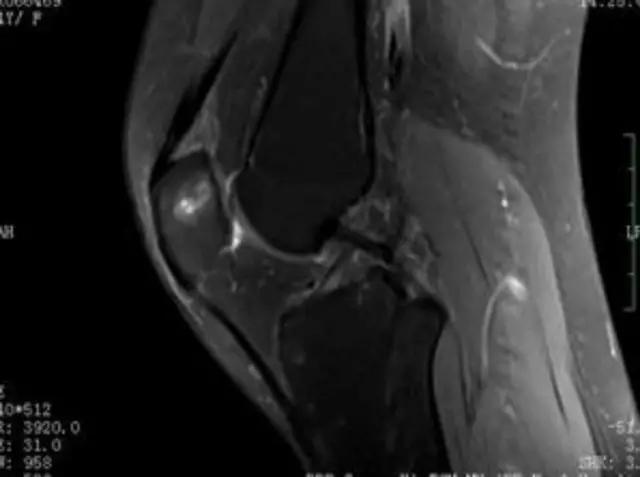

下图是同一个病人的MRI照片,MRI显示的内容更多,包括骨与软组织等,很多早期的、细微的病变都能清晰显示,其诊断报告对病人造成的影响也更大!

我们可能都不熟悉T1、T2,怎么办?当我们发现有问题后,利用照片上图像的对比,推测病变的可能也是一种诊断方法。病例:黄XX,女,39岁,左膝关节反复交锁1年。图1:肿物信号与骨信号一样图2:肿物信号与骨信号一样图3:肿物信号与骨信号不一样 肿物应该与骨相关,但不是骨性,推断:膝关节滑膜软骨瘤。手术后得到证实。